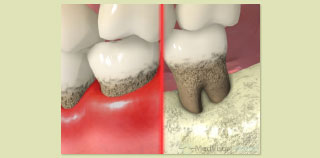

スケーリング・ルートプレー二ング

歯周病の基本的な治療です。初期の段階であれば歯肉縁下のプラークと歯石を徹底的に取り除くことにより多くの場合で歯周病は治癒します。